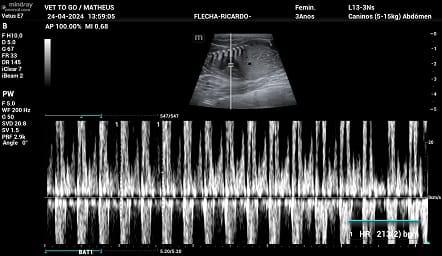

Ultrassom Gestacional Pet

A Vet To Go realiza Ultrassom Gestacional Pet em cachorros e gatos em clínicas e em domicílio.

Sobre o Ultrassom Gestacional em cães e gatos

A ultrassonografia em pets permite estimar a idade gestacional, data do parto, condições vitais do feto e desenvolvimento fetal.